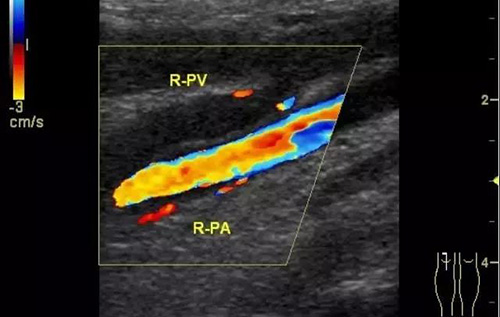

彩色普勒超聲診斷儀,線陣探頭,頻率7.5~10MHz。受檢查者先取仰臥位,患肢髖關(guān)節(jié)略外旋,大腿輕度外展且膝關(guān)節(jié)略曲,使整個(gè)下肢呈松弛狀態(tài)。自上而下順序檢查髂外、股總、股淺、股深及大隱靜脈;之后取俯臥位,檢查靜脈及小腿靜脈。以縱切和橫切顯示血管,灰階超聲主要觀察血管內(nèi)徑、管壁結(jié)構(gòu)及血栓情況,CDFI主要觀察管腔內(nèi)有無血流顯示、充盈缺損及血液返流情況,必要時(shí)擠壓小腿腓腸肌以利血流顯示。

彩超診斷下肢深靜脈血栓形成后綜合征具有無創(chuàng)、實(shí)時(shí)、動(dòng)態(tài)、重復(fù)性好、準(zhǔn)確率高的特點(diǎn),且能充分了解血管內(nèi)外的解剖學(xué)改變,觀察靜脈管壁、血流充盈、靜脈瓣返流程度以及側(cè)支循環(huán)是否建立和血栓的溶液情況,可直觀地觀察到血流動(dòng)力學(xué)改變,所以具有很高的使用價(jià)值。通過對(duì)治療前后聲像圖的對(duì)比,可以提示臨床的治療效果,對(duì)于臨床治療具有很大的指導(dǎo)作用。